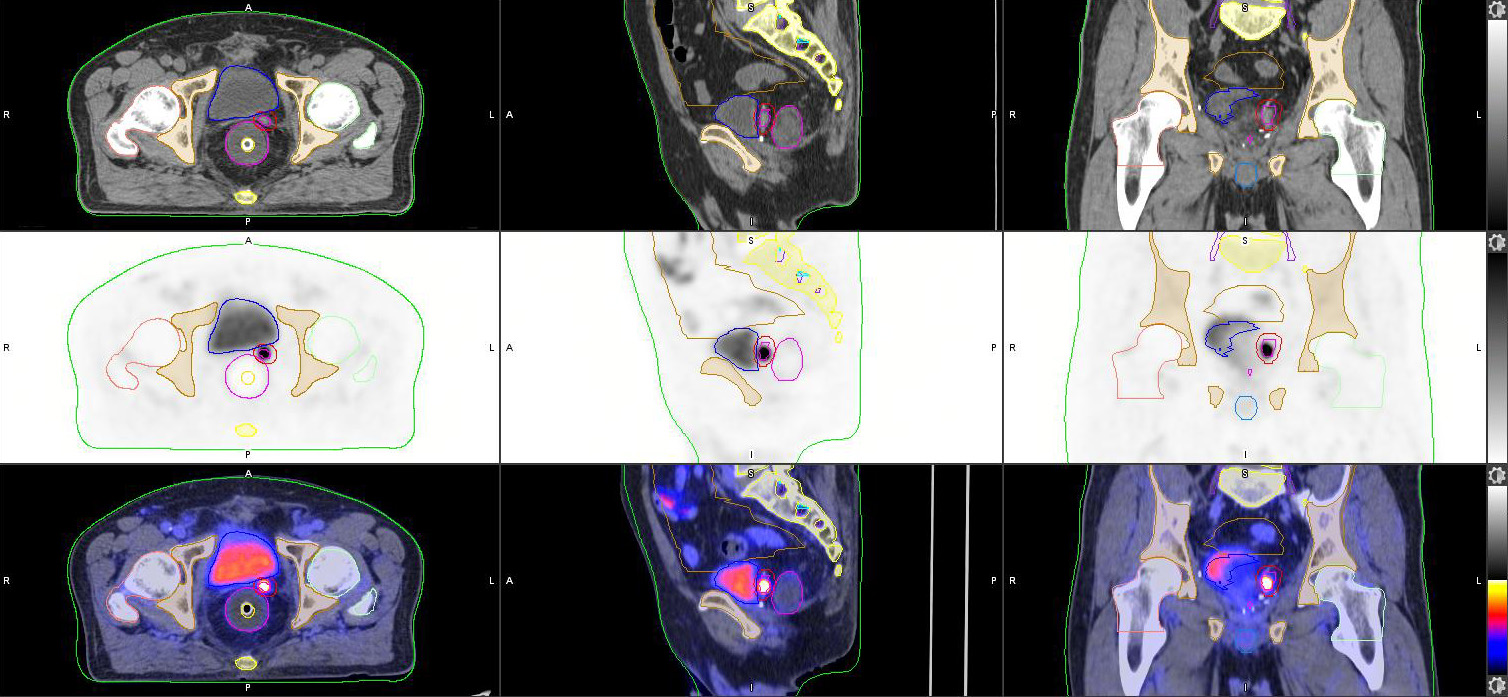

正电子/电脑双融扫描模拟定位 (PET/CT Sim) 为放射治疗疗程规划提供一站式新陈代谢评估及电脑扫描模拟定位 (CT Sim) 。放射治疗达到最佳效果的关键, 在於对肿瘤释放最大剂量的辐射及令健康组织免受损害。正电子/电脑双融扫描正好利用多样化正电子示踪剂,清晰地呈现目标肿瘤的新陈代谢变动丶量化其入侵性及定性其组织功能状态(如细胞分化及缺氧)。

部门的正电子/电脑双融扫描器配备SiPM技术,并外置激光定位系统及平面指标托板,可进行精准的同步空间配准及高解像度造影。一体化的正电子/电脑双融扫描数据 能 简化评估及模拟定位程序,为病人度身订造治疗方案。正电子扫描影像中的资讯(如肿瘤生物形态及功能数据)直接与电脑扫描定位影像整合,可用作计算及增加辐射剂量之用,更同时适用於 治疗前及治疗期间的中段评估 及 进行适应性放射治疗。